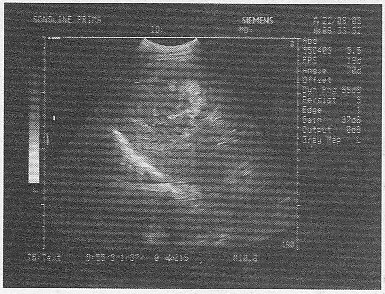

5.某患者25岁,高热,肝区疼痛。肝脏声像图表现如图,结合病史,最可能的诊断是

A.肝血管瘤

B.肝脓肿

C.肝硬化

D.肝癌

E.肝囊肿

正确答案:B 解题思路:高热,肝区疼痛,声像图显示肝内可见一无回声暗区,壁厚,内部回声不均匀。